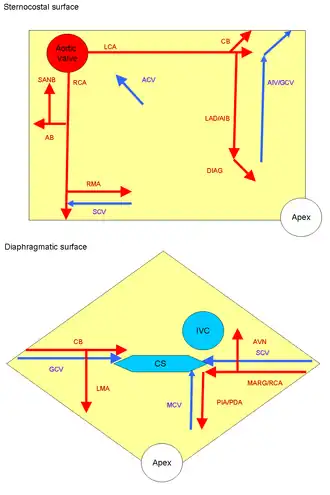

Arteries: RCA = right coronary AB = atrial branches SANB = sinuatrial nodal RMA = right marginal LCA = left coronary CB = circumflex branch LAD/AIB = anterior interventricular LMA = left marginal PIA/PDA = posterior descending MARG = left marginal AVN = atrioventricular nodal Veins: SCV = small cardiac ACV = anterior cardiac AIV/GCV = great cardiac MCV = middle cardiac CS = coronary sinus | |

Sternocostal surface of heart (right coronary artery visible at left)

Sternocostal surface of heart (right coronary artery visible at left)